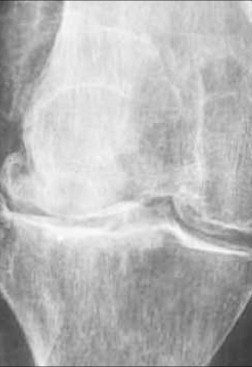

The management of chondral disease poses challenges due to its poor healing potential. Biomechanical and biological changes can accelerate degeneration, leading to end-stage osteoarthritis (OA).

The study, approved by the Ethics Committee, involved 30 patients with diffuse degenerative chondral lesions treated with autologous micro-fragmented adipose tissue between January and December 2014. Clinical evaluations were conducted at 3 years post-treatment.

The study demonstrates sustained benefits of autologous micro-fragmented adipose tissue in treating diffuse degenerative knee chondral lesions at mid-term follow-up, supporting its role as an adjunct in surgical procedures.